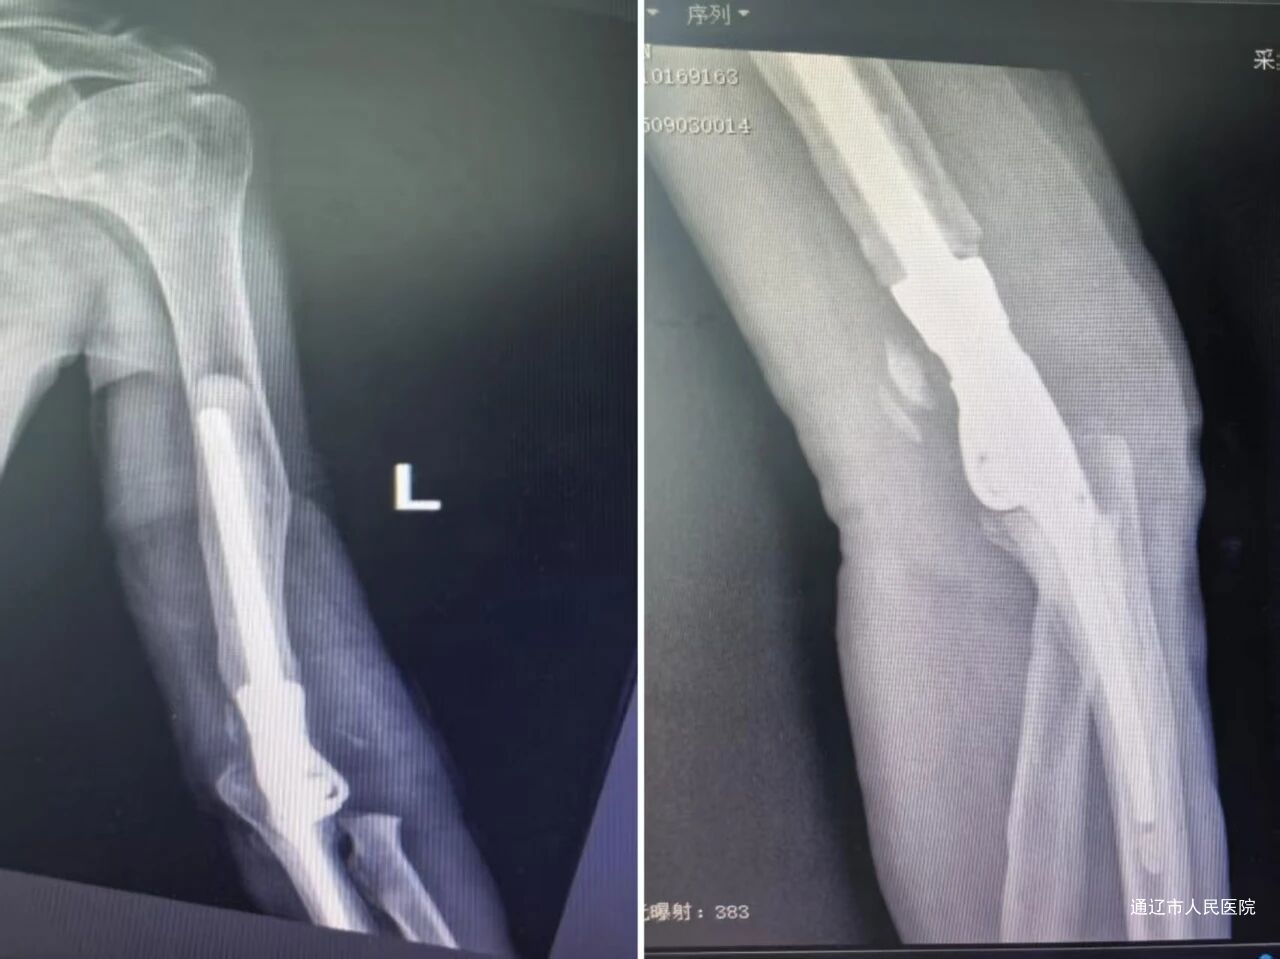

术后X线